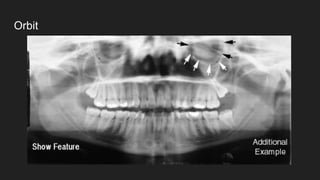

● Orbit

Orbit